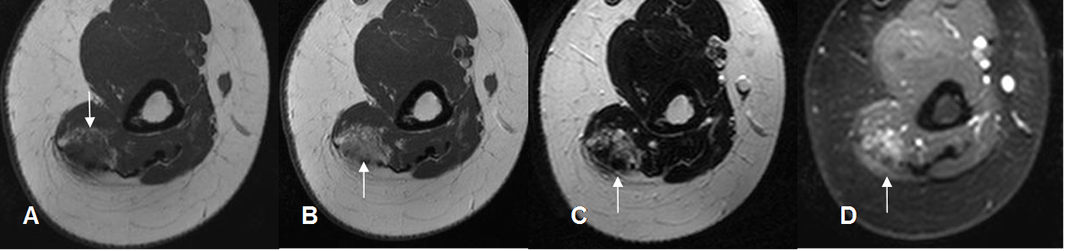

Fig 148. Hemangioma

A: RM axial en T1 Simple y B: RM axial en T1 con contraste. Lesión hipointensa de tejidos blandos en la parte posterior del brazo. Presenta zona hiperintensa anterior, por contenido graso o sangrado subagudo y que realza con el contraste.

C: RM axial en T2 y D: RM axial en STIR. Lesión hiperintensa, con áreas hipointensas (Flechas), por el contenido de hemosiderina.